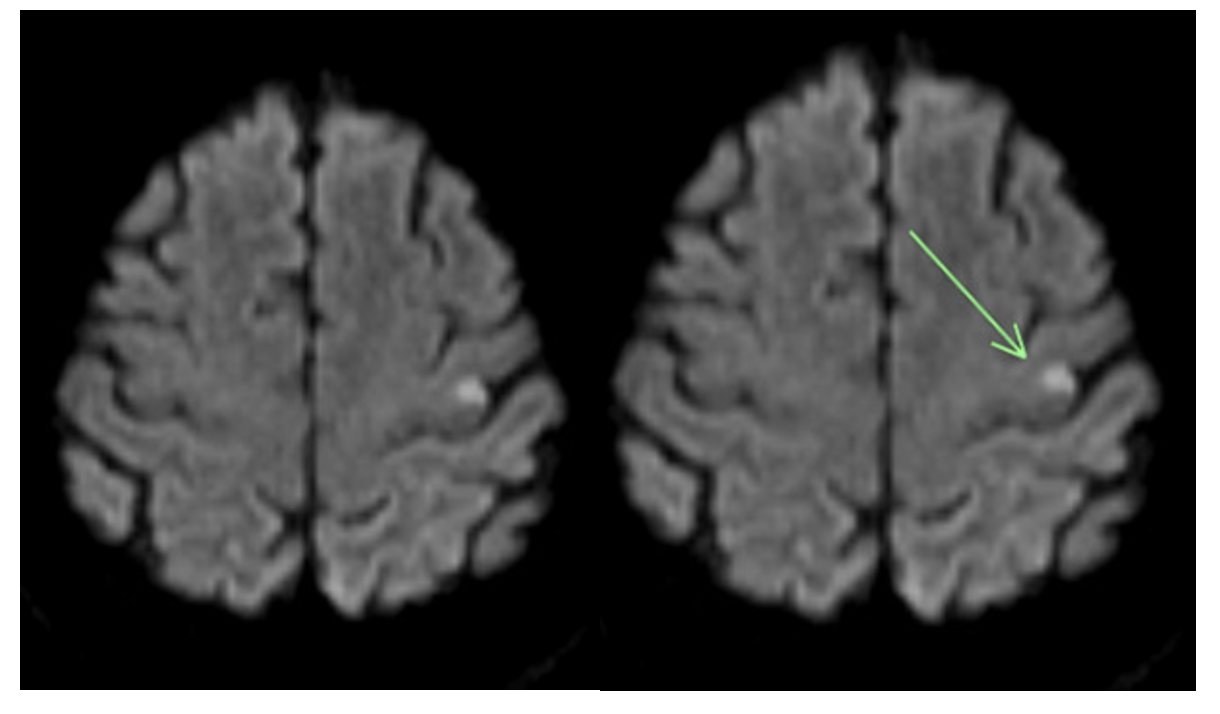

Given the small size of the carotid web, no intervention was performed. The patient was discharged home on the same medication regimen. A complete rheumatologic and hematology panel ruled out secondary causes of coagulopathy possibly causing recurrent thrombi. After 12 months, the patient presented following 10 minutes of left arm numbness and facial drooping with complete recovery at the time of presentation. MRI showed small acute cortical infarcts involving the left precentral gyrus and parietal lobe. Again, a complete workup was negative. This time, the patient was discharged adding 75 mg of clopidogrel to her regimen, but 4 months later she was readmitted with the same symptoms of 1-hour duration. She was given tPA, now a third time, and MRI showed acute stroke of the left medial cerebral artery territory. Again, workup failed to show a source of the recurrent strokes. Given the failure of dual antiplatelet therapy, clopidogrel was stopped and 5 mg of apixaban twice daily was added. After this medication adjustment, the patient has been stroke-free for 5 years, with consistent follow-up in clinic.

Recurrence of cardiovascular accidents (CVA) occurs frequently. Studies have demonstrated recurrence of CVA in 26% of patients within 5 years.3 This case reports a patient on antiplatelet therapy with recurrent CVA with no identifiable cause. Her stroke was classified as cryptogenic due to a lack of evidence of etiology despite repeated tests to rule out cardioembolic, aortoembolic, or atheroembolic causes. Since all the strokes occurred within the region of the left internal carotid artery (Figures 2-4), we suspect they were caused by the left internal carotid web. During DSA, the neurosurgeon noted in the operative note that the extracranial left carotid artery circulation exhibited normal caliber and course, with the exception of a very small, eccentric intimal web at the junction of the left internal carotid artery bulb and proximal cervical segment. While most carotid webs are found in the carotid bulb’s posterior margin, the carotid web in this case appeared in the anterior and distal aspect. Theoretically, a carotid web could form anywhere along the carotid artery where a thin, membrane-like shelf of tissue that extends from the wall to the lumen exists. The multitude of infarcts in the left internal carotid’s territory helps to support that this patient has a carotid web rather than a kinked or tortuous vessel, and that it has a probable role in stroke etiology.